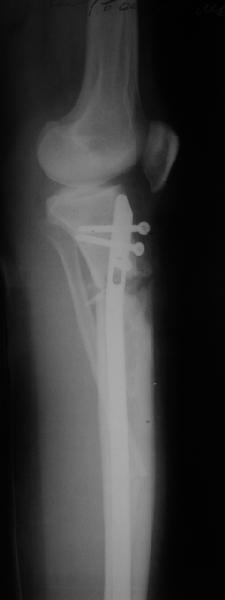

Продолжение обсуждения, начатого в октябре прошлого года (см. здесь) Наконец-то оперировали эту пациентку. Биопсию сделали - опухолевого ничего нет. Пока все участвовавшие в обследовании смежные специалисты и ортопеды сошлись, что это молокальная монооссальная фиброзная дисплазия. 20 марта наложили аппарат, сделали чрескожную остеотомию. К 3 апреля все докрутили. Сегодня заштифтовали. Начальные и итоговые снимки в приложении. Рекурвацию можно было еще немного больше устранить, и чуть кзади сместить диафиз. Но вроде и так ничего выглядит, по сравнению с тем, что было. Комментарии приветствуются.

Вопрос: почему дистально только один винт? Предполагаете ли динамизацию?

|

АС> Вопрос: почему дистально только один винт?

Второй тут можно было сделать динамический, но отломок очень уж длинный, и ротационной подвижности даже без винтов не будет.

АС> Предполагаете ли динамизацию?

Если не успеет срастись месяца за два, то этот винт и уберем.